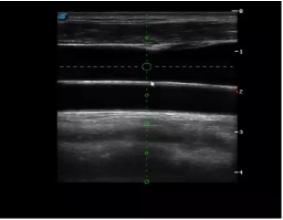

4  置管專用探頭

實時觀察穿刺針進(jìn)入血管的全過程,方便操作及較短的穿刺路徑,智能進(jìn)針尺寸提示,讓置管工作更加輕松,高效。

不同進(jìn)針路徑